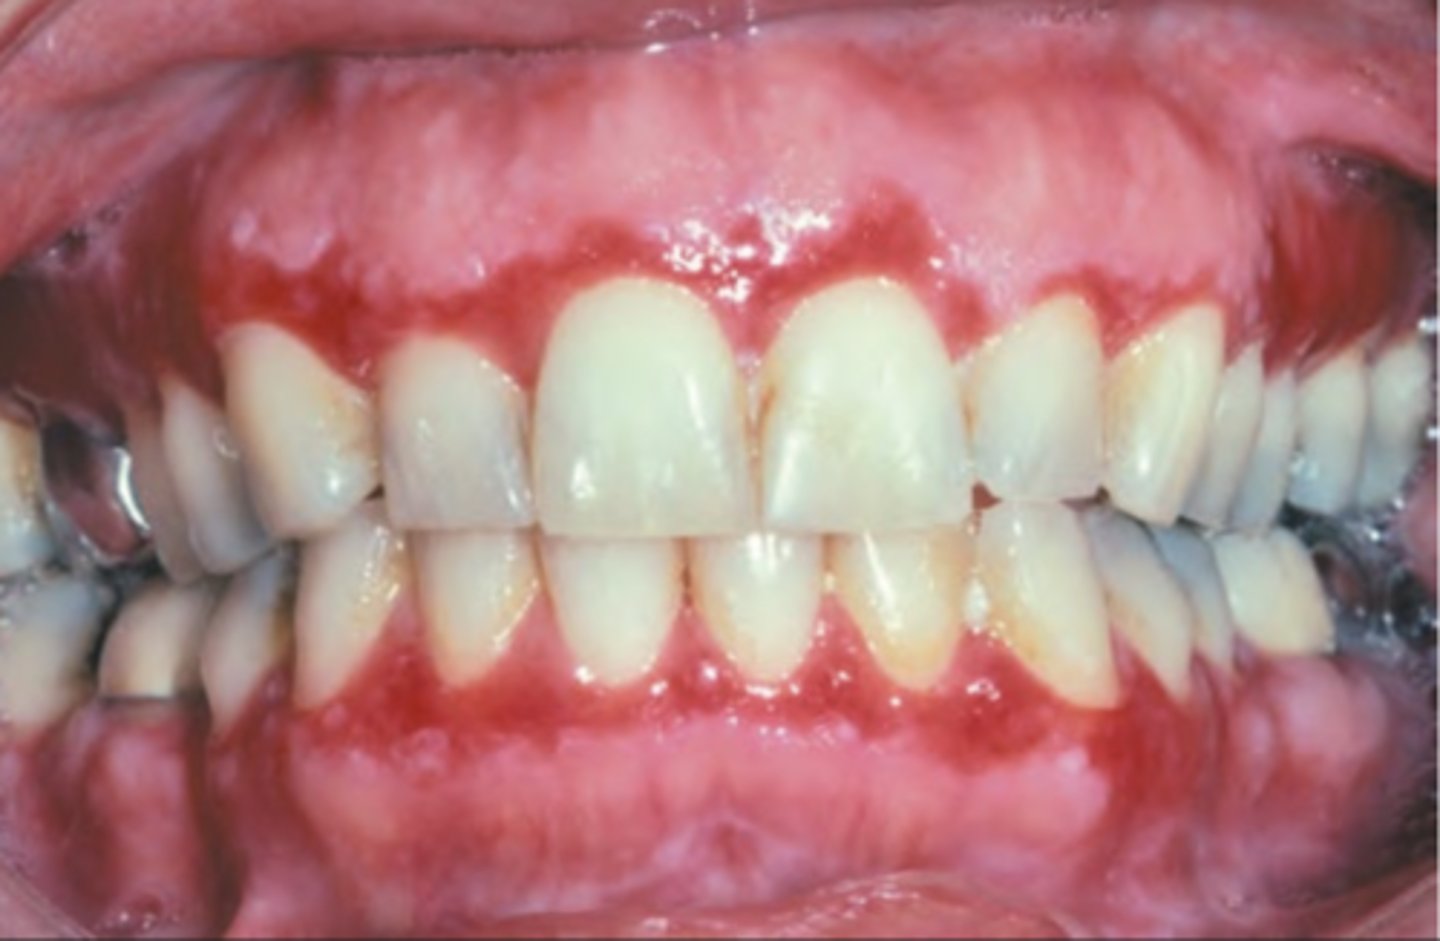

Pemphigus Vulgaris

Hint: Painful and long persisting superficial and ragged erosions affecting mucosal surfaces

Hint: Oral lesions are "First to show, last to go"

Hint: Flaccid vesicles & bullae that rupture quickly